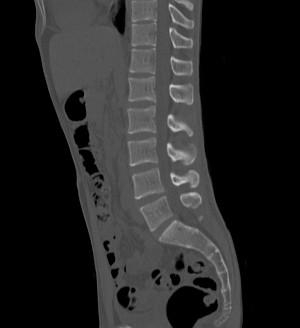

Поясничный отдел позвоночника

Грудной отдел позвоночника